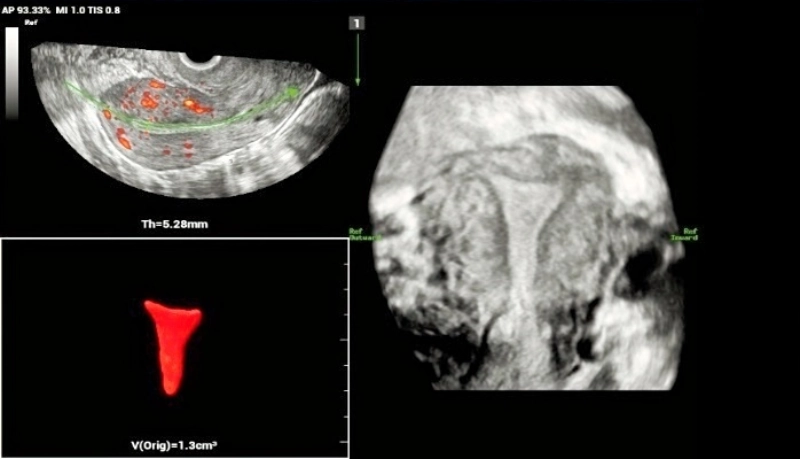

2. Arcuate uterus.

Use of Smart ERA in diagnosis of Mullerian duct abnormalities - Arcuate uterus

Smooth indentation of fundal endometrial canal, the depth of indentation is <1 cm.